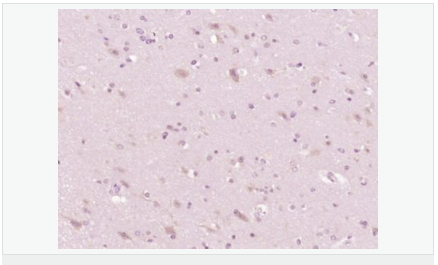

交叉反應:Human,Mouse,Rat(predicted:Pig,Cow,Horse,Rabbit) 推薦應用:WB,IHC-P,IHC-F,ICC,IF,ELISA

| 產品應用 | WB=1:500-2000 ELISA=1:5000-10000 IHC-P=1:100-500 IHC-F=1:100-500 ICC=1:100 IF=1:100-500 (石蠟切片需做抗原修復) not yet tested in other applications. optimal dilutions/concentrations should be determined by the end user. |